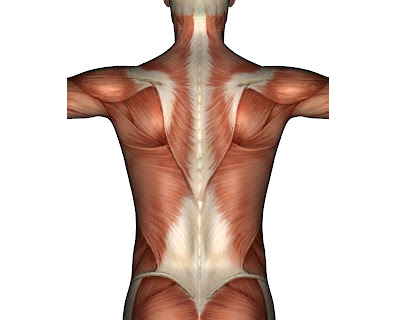

In the diagram below we can see the muscular connections between the lower/ upper parts of the spine and the shoulders. The chronic lower back pain that the person is experiencing may be due to a shoulder problem on the same or opposite side of the body. The shoulder problem can lead to an increased work load in the lower back ultimately leading to chronic pain. In this case then, the shoulder needs to be treated along with the lower back in order to get rid of the lower back pain.